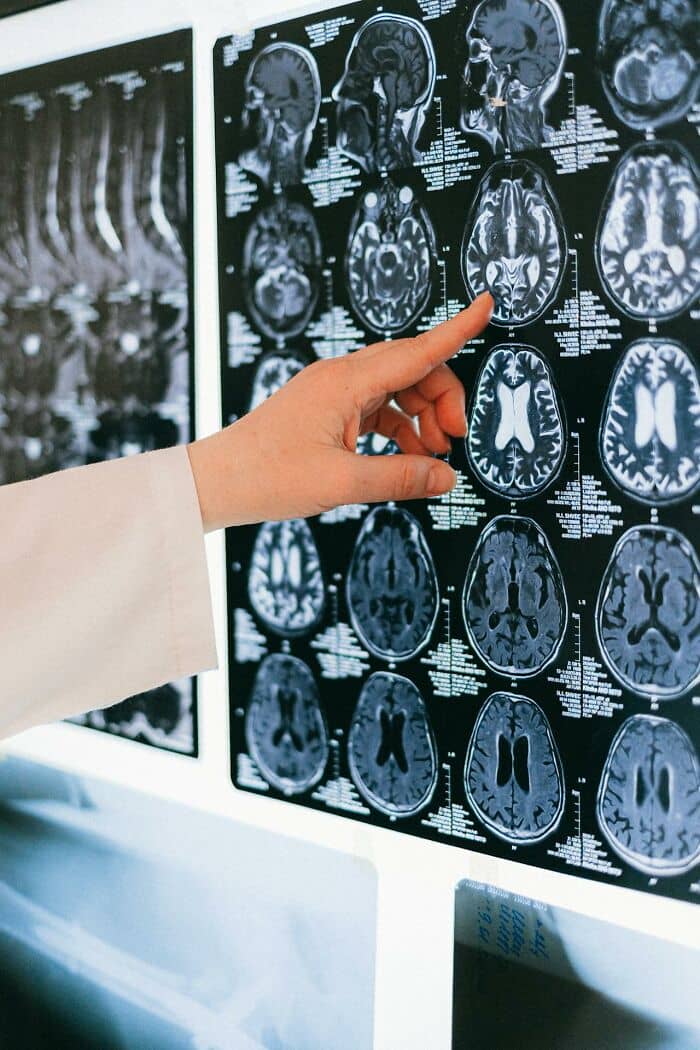

Young man comes in complaining of headache. I work in radiology.

We ask for history. Nothing to report, he says.

We scan his head. CT shows a bullet rattling loose inside his sphenoid sinus (kind of between the nasal cavity and the brain).

I asked the guy: “Have you ever been shot in the face?”

“Oh, yeah, I guess I forgot to mention that.”

To clarify, the guy had been shot in the face a few years earlier, never sought treatment for it. The bullet had somehow missed all the vital structures.